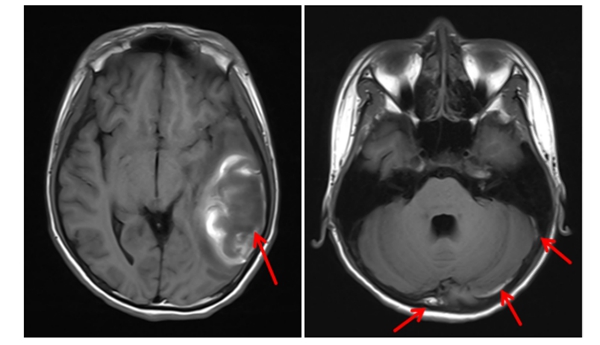

近日,中山大学附属第一医院(简称中山一院)广西医院放射影像科与儿科团队通力合作,通过联合会诊和精准的影像学分析,完成一例疑难病例的精准诊断,找出患者病因,并制定了科学合理的治疗方案。目前,患者已得到针对性治疗,病情稳定向好。12岁的小卓(化名)因持续呕吐、腹痛伴发热在当地卫生院接受“急性肠胃炎”对症治疗,但始终未见好转,最终来到我院儿科就诊。在我院住院期间,儿科主任黄雪琼在查房过...